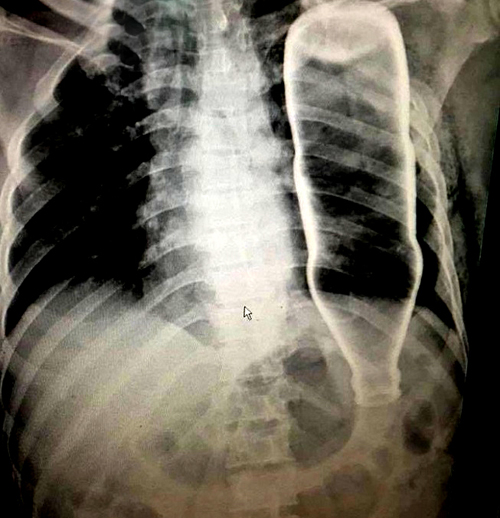

Hồi tháng 5, cú ngã khiến người đàn ông 53 tuổi ở Đà Nẵng gãy hai xương sườn và bị một dị vật xuyên ngực. Mãi khi đến bệnh viện, các bác sĩ mới biết đó là chiếc vỏ chai thủy tinh.

Các bác sĩ đã tiến hành chụp chiếu, kết quả chẩn đoán hình ảnh ghi nhận một vỏ chai làm bằng thủy tinh đang nằm gọn bên trong lồng ngực với tư thế đầu chai chúi xuống dưới. Để xuyên vào cơ thể, chiếc vỏ chai đã làm gãy 2 xương sườn của nạn nhân.